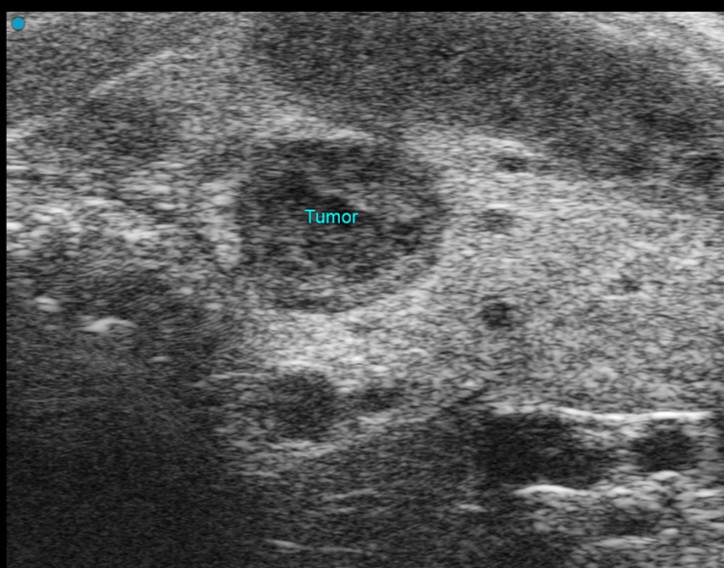

Custom services Oncology sonography (OncUS)

Using the Vevo F2 Lazr-X system, we monitor and quantify tumors in rodent models with high-resolution ultrasound and photoacoustic imaging. Our capabilities include:

- Morphological assessment: Tumor size and volume via 2D/3D imaging.

- Vascular analysis: Tumor vascularization with Power Doppler and blood flow measurement using PW Doppler.

- Advanced perfusion imaging: Nonlinear contrast with targeted or non-targeted microbubbles (Vevo MicroMarker) and quantification through Vevo CQ software.

- Photoacoustic imaging: Measurement of oxygen saturation and hemoglobin within tumors.

- Early detection: Photoacoustic contrast agents (wavelength 680–970 nm) for sensitive identification of small or early-stage tumors.

This comprehensive approach supports studies on tumor growth, angiogenesis, and therapy response.